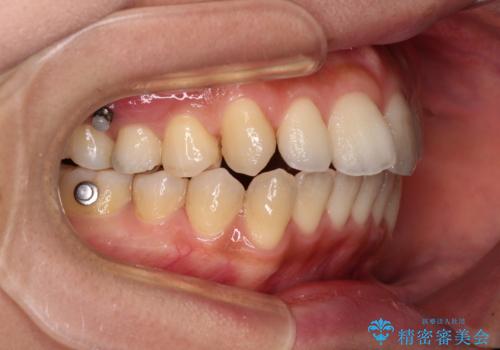

乳歯を抜歯し、舌側の永久歯を引っ張り出すこととしましたが、希望のインビザラインでは移動量が大きすぎて対応できない可能性があったため、ワイヤー装置にて改善することとしました。

ワイヤー装置にてある程度歯列が改善されたところで、上下をインビザラインにて矯正治療を行うこととしました。